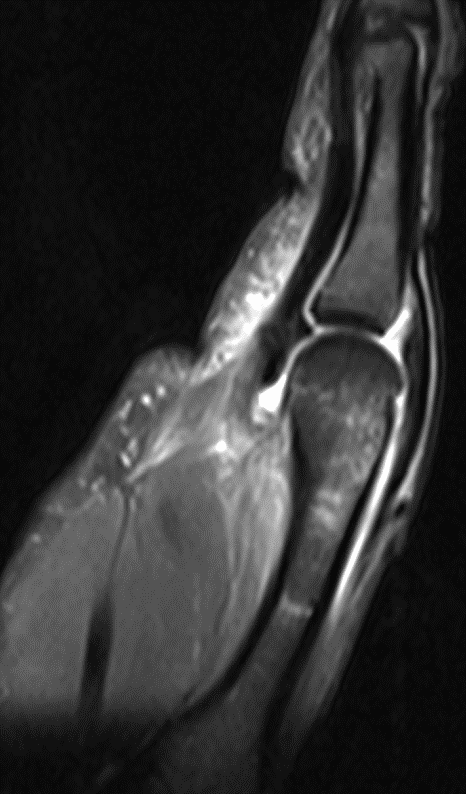

МРТ локтевого сустава

Травма в области локтевого сустава чаще, чем в других местах, осложняется нарушением кровообращения, при котором руку может спасти только раннее оперативное вмешательство. Диагностика заболеваний локтевого сустава обычно не вызывает затруднений, поскольку он хорошо доступен для обследования. Среди всех поражений локтевого сустава чаще всего встречаются травматические повреждения (особенно у спортсменов). Переломы костей, образующих локтевой сустав, хорошо диагностируются при рутинном рентгенологическом исследовании. Применение МРТ необходимо для визуализации повреждений суставной капсулы, связок и сумок локтевого сустава. Разрывы локтевой боковой связки представляют собой один из наиболее характерных видов спортивных травм и часто сочетаются с разрывами капсулы сустава, переломами внутреннего надмыщелка и венечного отростка локтевой кости. Прямыми МРТ признаками разрыва локтевой боковой связки являются прерывистость хода ее волокон, наличие жидкости в полости сустава и отек мягких тканей вокруг. Часто, как следствие острой или хронической травмы, развивается бурсит в области локтевого отростка с наличием выпота в поверхностной сумке, который отчетливо виден при осмотре пациента. Другим характерным повреждением локтевого сустава является эпикондилит - хроническое дегенеративно-дистрофическое заболевание, обусловленное постоянной травматизацией сустава у спортсменов (теннисистов, бейсболистов, игроков в гольф, боулинг и др.), а также у людей определенных профессий (каменщиков, маляров, швей и др.). На МРТ изображениях определяется утолщение или истончение сухожилий мышц, прикрепляющихся к надмыщелкам плечевой кости, частичные разрывы этих связок с выпотом и отеком вокруг.

Посттравматическая энтезопатия общего сухожилия мышц-разгибателей («латеральный эпикондилит»)